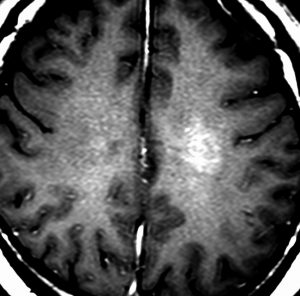

diffuse, infiltrative びまん性のもの

染み込むように左前頭側頭葉から島回に広がるAAです。T2/フレア像でにじむように広がり,ガドリニウム増強されません。グレード 2 (びまん性星細胞腫)と区別が難しいものです。

もちろん手術摘出できないもので,生検手術のみを行います。この大きさのものに60グレイの放射線治療をすれば高度の認知機能低下は避けられませんから,患者さんと照射線量をよくよく相談します。でもAAは放射線化学療法で長期生存が望めます。50-54グレイの線量が選択されます。